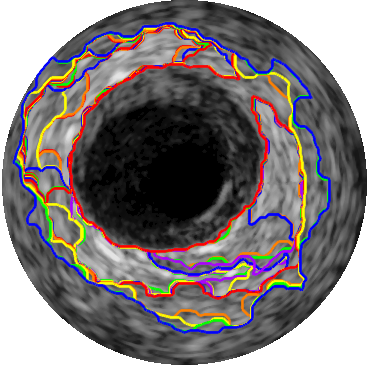

Our aim is to construct a vector that ultimately gives us the stability of the regions in terms of the length of the boundary, average intensity and entropy variation. As we can see in Figure 2(d), the boundaries of the regions are not smooth and are subject to large variations. Therefore, lumen and media regions should be selected among those regions that have more stable boundary length variations. Also, the average intensity of the regions should be stable enough (i.e., they should not change much over several subsequent regions). Entropy measure can be used in order to create a feature vector that is sensitive to textural information of the regions.

The local maxima of the stability score points to regions with high stability because the ratio of their current value to the change among their two neighbours is larger than the other surrounding elements. So, we select lumen and media from the detected local maxima. Specifically, a region with higher prominence value among the first two peaks is considered as lumen. If the IVUS image contains no artifacts, the media will be represented by the last detected peak. Based on our observation, the stability score of the images that contain serious artifacts have none or a small number of peaks since the presence of the artifacts interferes with the natural extraction of regions (see Figure 3(ii)). Therefore, when a small number of local maxima is detected, we consider the last extracted region as media. This process for an IVUS with no particular artifact is illustrated in Figure 3. The local maxima of the stability score indicates the regions for which the variation of the textural characteristics is more stable than their surrounding regions. As can be seen in Figure 3(i)(a), the second peak is selected as a suitable region for the lumen since it has a higher prominence than the first peak. Also, the region corresponding to the last peak of which is chosen as the media has been shown in Figure 3(i)(b).